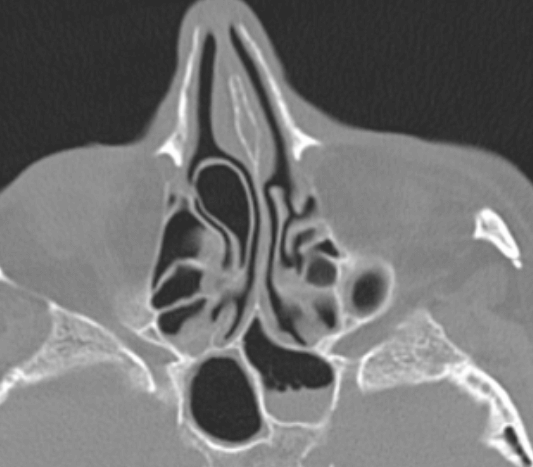

비중격이란 코의 중앙에 수직으로 위치하여 코 내부 공간을 좌우로 나누는 벽을 비중격이라고 합니다.

이 비중격이 휘어진 것을 비중격만곡이라고 합니다. 포유동물의 비중격은 반듯하지만 사람의 비중격은 다소 굽어 있는 것이 일반적이라 대부분의 사람들은 비중격이 좌측 또는 우측으로 휘어져 있습니다.

실제로 비중격이 굽은 사람이 굽지 않은 사람보다 훨씬 많기 때문에 어떻게 보면 일반적인 것이라고 할 수 있지만, 비중격 만곡으로 인해 코막힘, 후비루, 수면 장애, 수면 무호흡 등의 건강 이상 증상이 있을 때에는 '비중격 만곡' 질환이라고 할 수 있습니다.